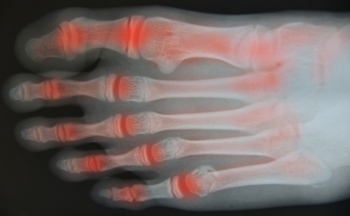

Stress fractures occur in the foot and ankle when muscles in these areas weaken from too much or too little use. The feet and ankles then lose support when walking or running from the impact of the ground. Since there is no protection, the bones receive the full impact of each step. Stress on the feet can cause cracks to form in the bones, thus creating stress fractures.

Stress fractures occur frequently in individuals whose daily activities cause great impact on the feet and ankles. Stress factors are most common among:

Pain from the fractures occur in the area of the fractures and can be constant or intermittent. It will often cause sharp or dull pain with swelling and tenderness. Engaging in any kind of activity which involves high impact will aggravate pain.